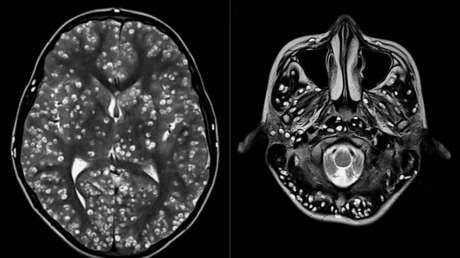

Tras practicarle una resonancia magnética y exámenes de ultrasonido, los especialistas encontraron que la corteza cerebral y el tronco encefálico del paciente estaban llenos de larvas.

El muchacho padecía neurocisticercosis, una enfermedad parasitaria originada cuando una persona ingiere huevos microscópicos de una tenia porcina y que afecta al tejido muscular. De ahí los parásitos se propagan al cerebro. Los personas infectadas pueden pasar mucho tiempo sin presentar síntomas.